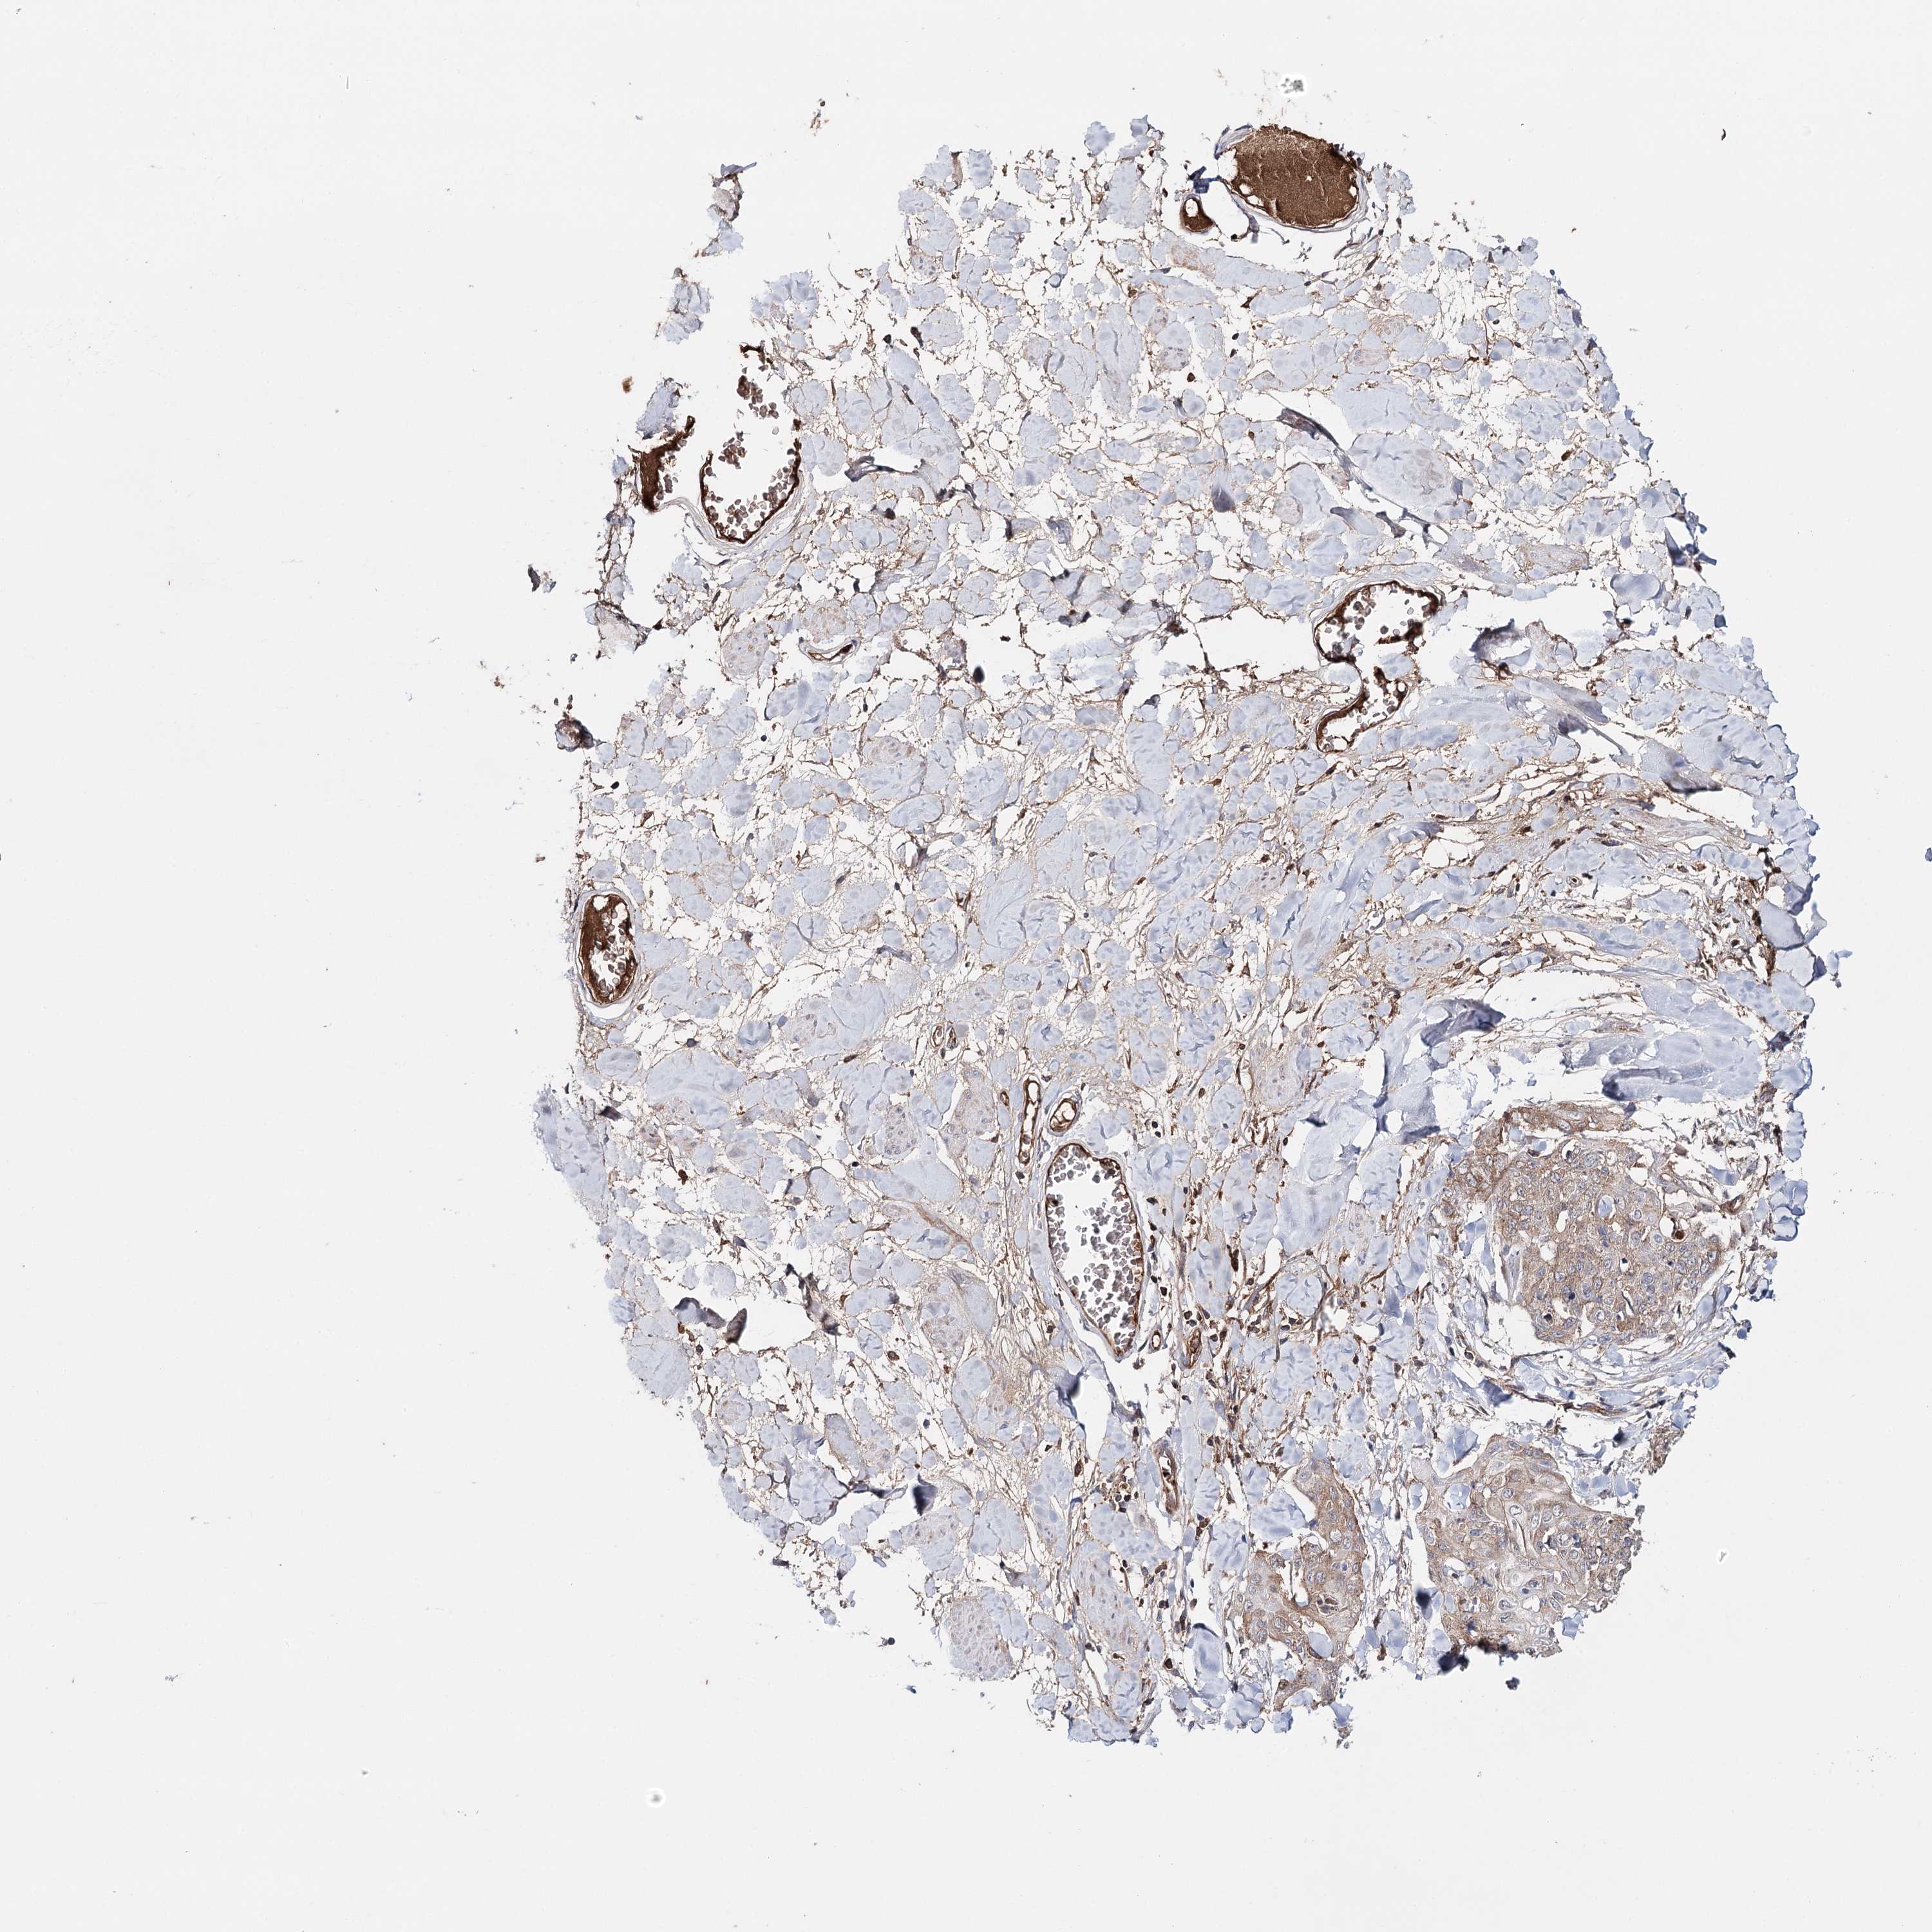

SKIN CANCER - Protein expressioni

A mouse-over function shows sample information and annotation data. Click on an image to view it in a full screen mode. Samples can be filtered based on level of antibody staining by selecting one or several of the following categories: high, medium, low and not detected. The assay and annotation is described here.

Antibody stainingi

Antibody staining in the annotated cell types in the current human tissue is reported as not detected, low, medium, or high, based on conventional immunohistochemistry profiling in selected tissues. This score is based on the combination of the staining intensity and fraction of stained cells.

Each image is clickable and will lead to virtual microscopy that enables deeper exploration of all samples and also displays staining intensity scores, fraction scores and subcellular localization as well as patient and tissue information for each sample.

Antibody CAB037334

Staining

High

Medium

Low

Not detected

Intensity

Strong

Moderate

Weak

Negative

Quantity

>75%

75%-25%

<25%

None

Location

Nuclear

Cytoplasmic/membranous

Cytoplasmic/membranous,nuclear

Basal cell carcinoma